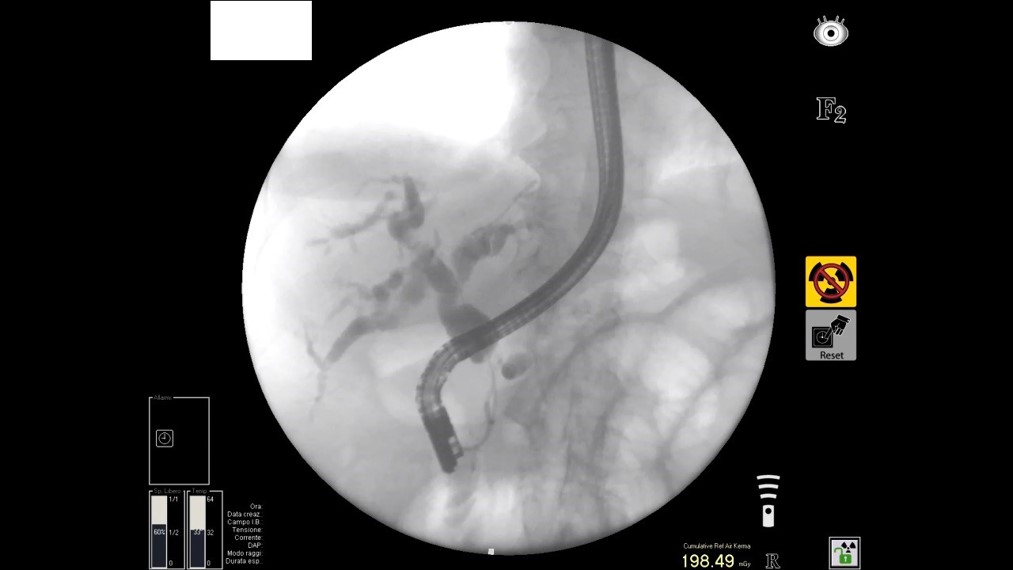

All patients underwent ERCP in the supine or lateral position using a standard duodenoscope. After successful biliary access, minimal biliary sphincterotomy was performed in all patients prior to metal stent insertion. The length of the stent was chosen according to the extension of the stricture in order to release the proximal end 1–2 cm beyond the stricture, and always below the hilum, with the distal uncovered portion outside the papilla. After estimating the length of the stricture during cholangiography (Figure 2), the endoscopist chose between the available types of Niti-S Biliary Covered stent (Both Bare Type) (Taewoong Medical Co. Ltd., Korea) (diameter of 10 mm and length from 4 to 8 cm) (Figure 3A and 3B).

Figure 2

Figure 2. Distal biliary malignant stenosis in a patient affected by pancreatic carcinoma.